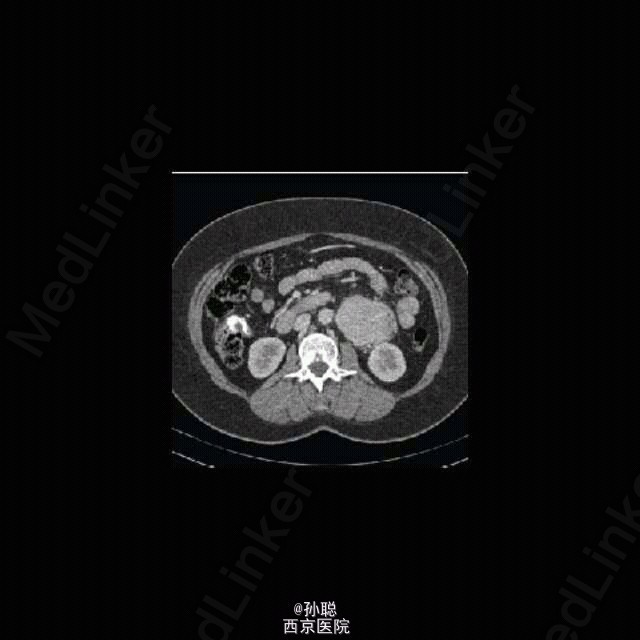

一名 40 岁女性因无症状左肾肿块入住外科病房。病灶因妇科 B 超体检偶然发现。既往无相关病史。患者无腹部不适、腰背痛、消瘦、汗出、疲劳或发热。体格检查无殊。浅表淋巴结和脏器未及肿大。血常规和生化等实验室检查均正常。 进一步查腹部 CT 显示左肾旁一 7.6×5.3×12cm 肿块,血供丰富、边界清,未侵犯周围组织。腹腔其余部位、纵膈和肺部未见肿瘤。 行剖腹探查术。术中将病灶完整地自左侧腹部取出。病理诊断明确 Castleman’s 病,透明 / 血管变异。术后恢复顺利,患者于术后第 5 日出院。术后一年患者健康状况良好。CT 随诊无复发或其它病变。